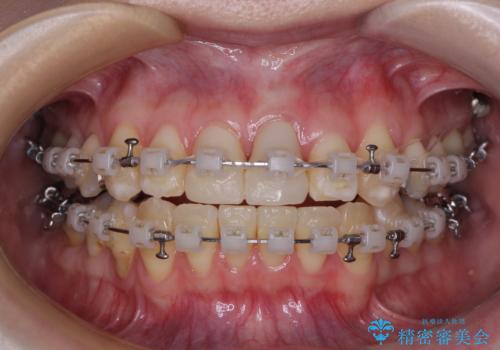

- 矯正装置

- クリアブラケット

ワイヤー装置、マウスピース、どちらの装置でも治療は可能でしたが、マウスピース矯正の自己管理の煩わしさを懸念され、ワイヤー装置にて矯正治療を行うこととしました。

前歯の黒い縁は、矯正治療後にオールセラミッククラウンにて改善することとしましたが、いち早く目立たなくしたいとのことで、事前に矯正治療用仮歯に置き換えてから矯正治療を開始しました。

前歯を早々に仮歯に置き換えたことで、矯正治療に意欲的に臨んでくださいました。